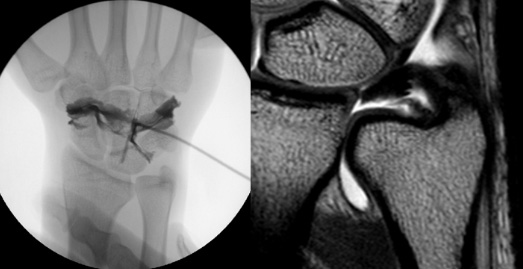

· 일반 X-ray 촬영을 통하여 원위요척골 관절 간격의 변화를 확인하고 이상이 있을 시 MRI 와 CT검사를 시행하여 확진을 할 수 있습니다.

· 본원에서는 검사 소견과 수술시 관절조영술을 시행하여 보다 더 정확한 진단을 통하여 적절한 치료를 시행하여 통증과 운동기능 및 안정성에서 좋은 결과를 얻고 있습니다.

손목 사용이 많은 환자나 보존적 치료에 효과가 없는 경우에는 수술적 치료를 고려할 수 있습니다. 수술 전 MRI나 수술 당시 손상된 부위에 따라 수술방법이 달라지며, 만약 원위요척골 관절의 불안정성이 유발된 경우에는 TFCC의 골봉합 방법이 필요합니다. 전 세계적으로 대략 3가지 방법(관절내시경으로 봉합하는 방법, 전통적인 개방적 방법, 두가지를 혼합한 방법)이 있습니다.

본원에서는 국내에서 선도적으로 두 가지를 혼합한 관절내시경을 이용한 골터널 고정방법을 시행하고 있으며, 많은 환자들에게서 좋은 결과를 보이고 있습니다.